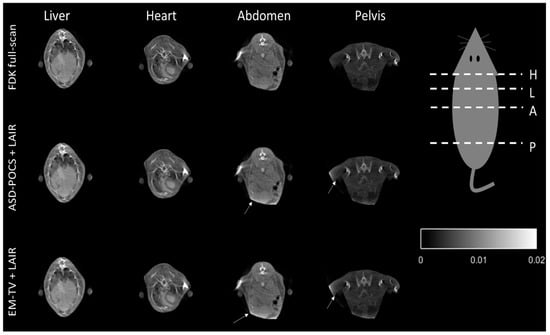

Figure 9 displays a cross-sectional image of the contrast-injected mouse after the FDK-based reconstruction and proposed LAIRs were applied. It shows that the LAIR method represents an excellent choice for reconstructing the liver, heart, abdomen and pelvis portion without changing their shape forms and with high IQ. The results demonstrate that our IR methods are suitable for general cone-beam CT system but there are still some artifacts present (ring-artifact and beam-hardening effect) and we will resolve these in the near future (see Figure 8 and Figure 9).

Figure 9.

The tomographic images of the contrast-injected mouse, which cross over into the liver (L), heart (H), abdomen (A) and pelvis (P) regions, reconstructed using the conventional FDK and the two LAIR algorithms. The display is in the range of [0, 0.02].

This result supports us to prove that combining our proposed stopping criteria with the LAIR methods can automatically achieve optimal IQ similar to FDK reconstruction without deformation in standard mode. Figure 8 presents some remnants of fading star-shaped artifacts in the FDK reconstructed image. The IR methods can efficiently reduce most artifacts because they update the difference from iteration to iteration. However, if there is inconsistent data, the artifacts will be worse. The truncation artifact observed in Figure 9 may be caused by external-FOV data from the binary classification process; the outside-of-FOV mask (indicated by arrows) used on the initial FDK image cause data inconsistencies when performing re-projections and artifact enhancement during the forward-projection process in the IR methods.